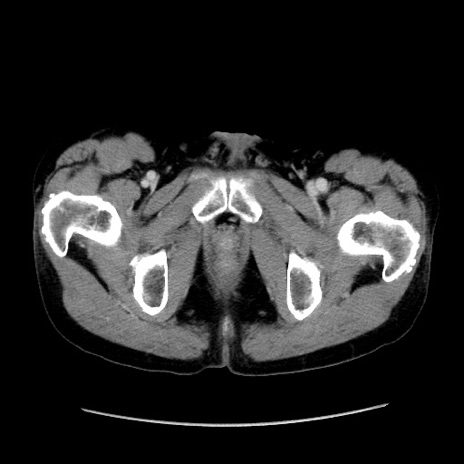

症例37(横断像)

【症例】40歳代 男性

【主訴】腹痛

【現病歴】4時間ほど前に電車に乗車中に臍部上より腹痛出現。徐々に増悪し起立困難となり、救急外来受診。生ものは数日食べていない。今朝お雑煮を食べた。

【身体所見】BT 36.8℃、BP 117/84mmHg、HR 91/min、SpO2 97%、苦悶様、腹部:臍上部広範囲圧痛あり、反跳痛±

【データ】WBC 8100、CRP 0.03